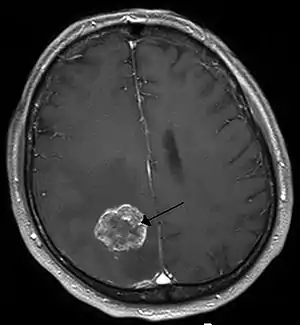

Other namesIntracranial neoplasm, brain tumour

Brain metastasis in the right cerebral hemisphere from lung cancer, shown on magnetic resonance imaging